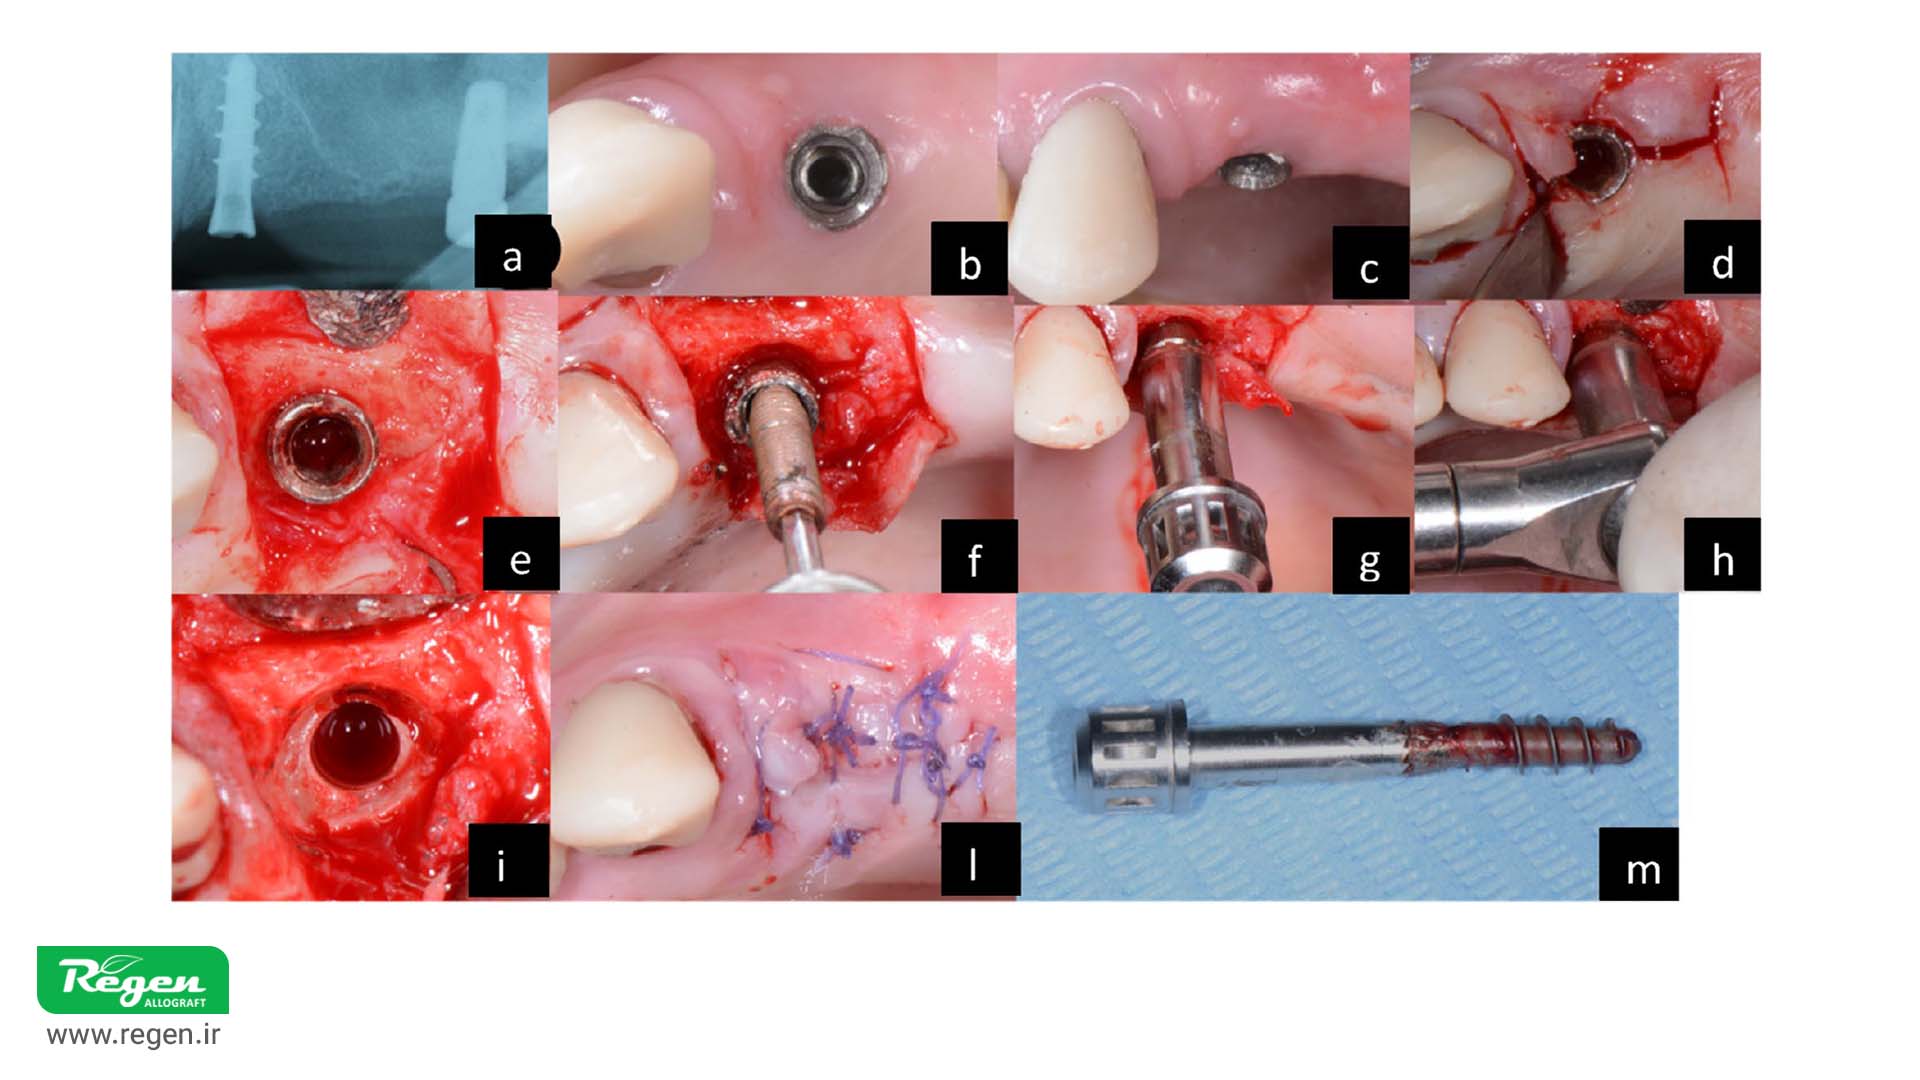

این تصویر به بررسی تکنیکهای موجود برای برداشت ایمپلنت دندانی میپردازد

تکنیک ضدگشتاور (CTRT) در برداشت ایمپلنتهای دندانی

توانایی برداشت ایمپلنت با تکنیک ضدگشتاور به عوامل مهمی بستگی دارد، از جمله نوع اتصال ایمپلنت، شکل و هندسه آن و درجه اُسواینتگریشن اطراف ایمپلنت. این روش یکی از مؤثرترین و محافظهکارانهترین تکنیکها برای برداشت ایمپلنت است؛ با این حال، شرایط خاصی باید رعایت شود:

- اتصال ایمپلنت باید سالم باشد.

- ایمپلنتهای باریک ممکن است در معرض شکستگی قرار گیرند.

- در صورت نامناسب بودن اتصال، استفاده از این روش توصیه نمیشود.

اجزای کیت CTRT شامل پیچ اتصال، درایور مخصوص پیچاندن، و گشتاورسنج است که امکان اندازهگیری دقیق گشتاور مناسب برای برداشت را فراهم میکند. این کیتها معمولاً یونیورسال بوده و با اکثر برندهای ایمپلنت سازگارند. نمونههایی از این کیتها عبارتاند از: Straumann® Counter-Torque Kit، Neo Fixture Remover Kit و BTI Implant Extraction System.